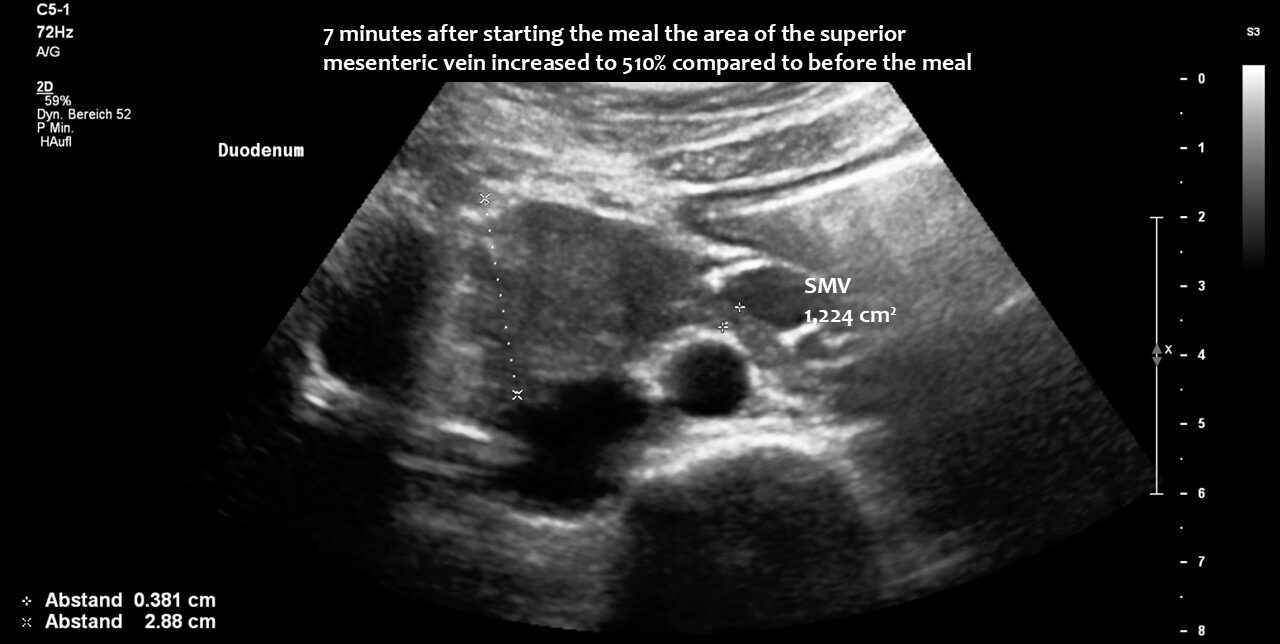

The superior mesenteric vein appeared normal when the stomach was empty, but showed enormous 5-fold enlargement of its transsectional area after food was consumed. The enlarged vein prevented food from passing across the aorta, as the stomach pushed the superior mesenteric vein against the duodenum, narrowing the passage to such an extent that the descending duodenum enlarged to 38 mm (the usual width is less than 20 mm). The patient reported substantial pain in the area of the distended duodenum, below the right rib cage.

Enlargement of the superior mesenteric vein can be observed as early as five minutes after eating, progressing to fivefold enlargement of the transsectional area after seven minutes.

Here, the unique mechanism causing compression of the duodenum by the enlarged superior mesenteric vein is demonstrated. In contrast to conventional SMA syndrome, the superior mesenteric vein acts as a pillar against which the aorta presses, thus obstructing the duodenum. It is important to be aware of the variability in the position of the superior mesenteric artery in patients with a flat abdominal cavity. When the stomach is full, it may shift further to the left (or right) of the SMA than in the fasting position.